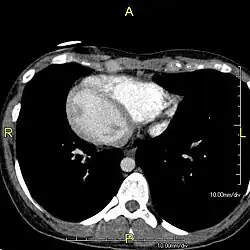

Situs inversus (also called situs transversus or oppositus) is a congenital condition in which the major visceral organs are reversed or mirrored from their normal positions. The normal arrangement of internal organs is known as situs solitus. Many people with situs inversus have no medical symptoms resulting from the condition, although cardiac problems are the most common complication. Until the advent of modern medicine, it was usually undiagnosed.

Situs inversus is found in about 0.01% of the population, or about 1 person in 10,000. In the most common situation, situs inversus totalis, it involves complete transposition (right to left reversal) of all of the viscera. The heart is not in its usual position in the left chest, but is on the right, a condition known as dextrocardia (lit. 'right-hearted'). Because the relationship between the organs is not changed, most people with situs inversus have no associated medical symptoms or complications.[1]

Effect on anatomy

The condition affects all major structures within the thorax and abdomen. Generally, the organs are simply transposed through the sagittal plane. The heart is located on the right side of the thorax, the stomach and spleen on the right side of the abdomen and the liver and gall bladder on the left side. The heart's normal right atrium occurs on the left, and the left atrium is on the right. The lung anatomy is reversed and the left lung has three lobes while the right lung has two lobes. The intestines and other internal structures are also reversed from the normal, and the blood vessels, nerves, and lymphatics are also transposed.

If the heart is swapped to the right side of the thorax, it is known as "situs inversus with dextrocardia" or "situs inversus totalis". If the heart remains on the normal left side of the thorax, a much rarer condition (1 in 2,000,000 of the general population), it is known as "situs inversus with levocardia" or "situs inversus incompletus".

Diagnosis of situs inversus can be made using imaging techniques such as x-ray, ultrasound, CT scan, and magnetic resonance imaging (MRI).[9]